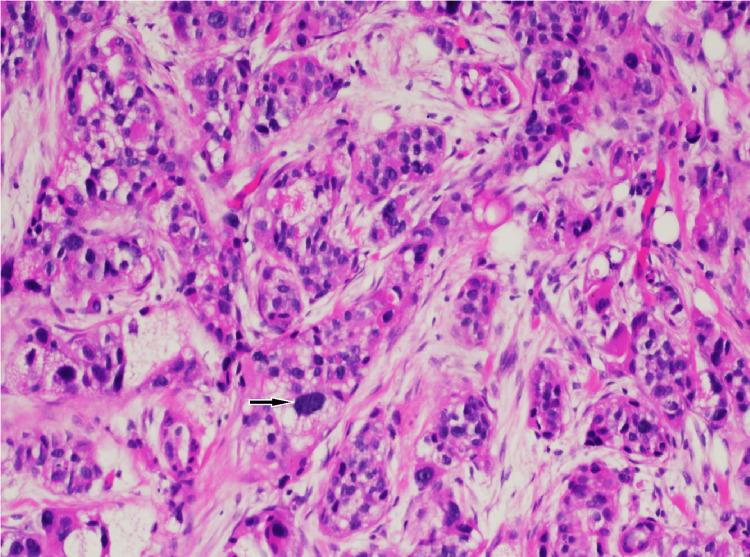

We describe a case of pathology-proven invasive lobular breast cancer (ILC) arising in a scar over 15 years after lumpectomy for previous invasive ductal carcinoma (IDC). The tumor was detected on screening mammography as a new focal asymmetry at the scar site and confirmed at diagnostic mammography. Ultrasound demonstrated an irregular, shadowing, hypoechoic mass at the scar site. Ultrasound-guided biopsy revealed poorly differentiated invasive lobular carcinoma. MRI and CT showed an irregular mass with pectoralis muscle invasion. Multimodality imaging findings are described. This is the first case to our knowledge reporting multimodality imaging findings of a breast cancer developing at the site of a surgical scar that is histologically different from the originally resected cancer.

我们描述了一例经病理证实的浸润性小叶乳腺癌(ILC)病例,该病例发生于先前因浸润性导管癌(IDC)行肿块切除术后15年以上的瘢痕处。肿瘤在筛查乳腺X线摄影中被检测为瘢痕部位新出现的局灶性不对称,并在诊断性乳腺X线摄影中得到证实。超声显示瘢痕部位有一个不规则、有阴影、低回声肿块。超声引导下活检显示为低分化浸润性小叶癌。MRI和CT显示有一个不规则肿块,侵犯胸大肌。描述了多模态成像结果。据我们所知,这是首例报告手术瘢痕部位发生的组织学上与最初切除的癌症不同的乳腺癌的多模态成像结果的病例。